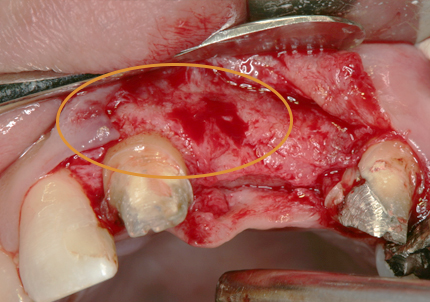

3. 右上1番・左上2番 SST(ソケットシールドテクニック)

【右上1番SST 口蓋側歯根の抜歯】

【左上2番 SST 口蓋側歯根の抜歯】